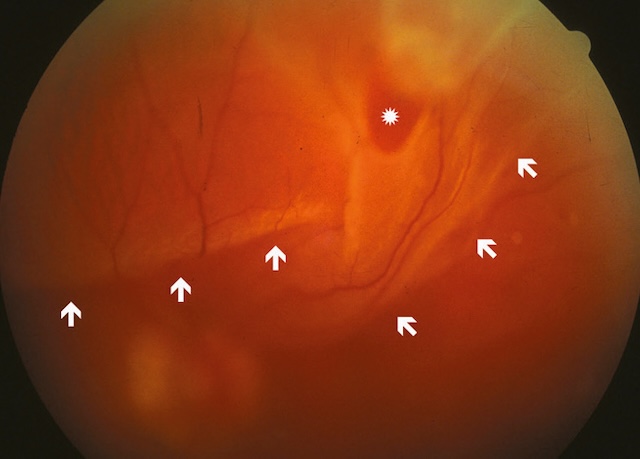

Fig. 8.17 Aspect du fond d’œil dans un décollement de la rétine secondaire à une volumineuse déchirure située en temporal supérieur.

Limites du décollement (flèches), déchirure (étoile).Cette image montre un fond d’œil typique d’un décollement de la rétine, secondaire à une large déchirure localisée dans le quadrant temporal supérieur. On distingue nettement une zone de soulèvement rétinien, marquée par un plissement des vaisseaux et une déformation de la trame vasculaire normale. Les flèches blanches indiquent la limite ondulée de la rétine décollée, qui prend un aspect légèrement opalescent et bombé. La lumière réfléchie en haut de l’image correspond à une condensation vitréenne ou à une traction localisée. L’ensemble du champ rétinien apparaît altéré, avec des zones de rétraction et une perte de netteté périphérique, caractéristiques d’un décollement évolutif. Ce tableau clinique nécessite une prise en charge rapide pour éviter une atteinte irréversible de la fonction visuelle.